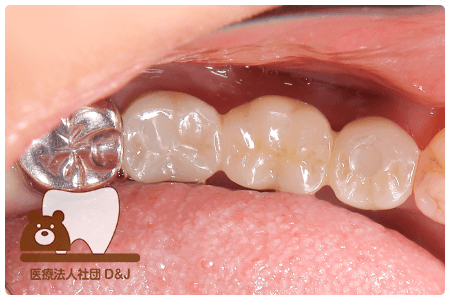

治療前

治療後

治療前

治療後

治療前

治療後

53歳 女性

- 治療内容

- 療内容奥歯にインプラントの埋入

- 治療期間

- 5ヶ月

- 費用

- 自費

インプラント体 1本:275,000円(税込)

インプラント上部構造(ジルコニア)2本:1本110,000円(税込)×2本=220,000円(税込)

(R8.3月時点)

- その他の治療の費用は含まれておりません。

- リスク・副作用

- インプラントは外科手術を伴うため、術後に腫れや痛み、出血、感染が生じることがあります。術後の指示を守らない場合、症状が悪化する恐れがあります。また、治療後に口腔内の清掃や定期的なメインテナンスを怠ると、インプラント周囲粘膜炎やインプラント周囲炎を引き起こすことがあり、インプラントの脱落につながる可能性があります。